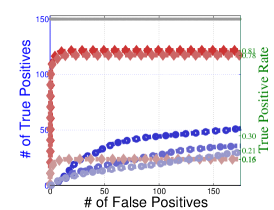

To understand the performance of this standard method, we present a small preview of our simulation study discussed later in Section 4. Briefly, we assume that each subject graph in group follows a small-world structure on nodes; in group , there are in addition 150 differential edges, meaning that and for all differential edges, . We generate data according to this model with time points and subjects in each group. Figure 1 illustrates the results of this standard approach as well as our new procedure, , which we will introduce later in Section 3. Part (a) gives ROC curves for the number of false positives verses true positives as each sequential test is rejected; parts (b) and (c) give the adjacency confusion matrix illustrating where the true and false positive as well as false negative edges are detected in the graph structure.

Our motivating simulation shows that the standard approach performs terribly in terms of both error control and statistical power. While the magnitude of the poor performance of this approach may seem astonishing, the poor performance should come as no surprise: The inferential procedure (e.g. test statistics) of the standard approach assume a one-level model that would be appropriate when the subject graphs are fixed and known or directly observed quantities. When these subject networks are unobserved, however, and must be estimated from finite data, these one-level test statistics are incorrect for our two-level problem. Specifically for two-level problems, the variance of parameters estimated by incorrectly assuming a one-level models is underestimated. For our problem, the extra source of variability arises from the graph selection procedure; we discuss challenges associated with this subsequently in Section 2.2. Incorrect variance estimates, however, are not the only problem with the standard approach: A more subtle problem arises from the fact that the proclivities of graph selection procedures for the Gaussian graphical model lead to biased estimates of the edge proportions, . As discussed in Section 2.3 and seen in Fig 1, graph selection false positives and false negatives do not occur at random throughout the network structure, leading to biased group level estimates.

Hence, the first term represents variability across subjects in group and the second term represents the variability associated with the selection procedure within subject , a quantity that we assume to be constant across subjects in each group . Consider now what happens if our true model follows this two-level Beta-Binomial model, but as with the standard approach, we use a one-level Binomial model and associated two-sample test statistic. The variance is thus underestimated and the test statistic is overoptimistic. Then, when inference is conducted for the population mean , using the incorrect Binomial model leads to inflated Type I error rates; this behavior has been well-documented (Weil, 1970; Liang and Hanfelt, 1994). Hence, failure to use the correct two-level model which accounts for the two levels of network variability partially explains the high error rates of the standard procedure observed in Figure 1.

In Figure 4 and Table 1, we present our main simulation results comparing to the two variations of our method and the standard approach for three network structures and Case I and II type differential edges. First for Figure 4, we report results in terms of operating characteristics averaged across 50 replicates with the number of true positives (y-axis) plotted against the number of false positives (x-axis) for each test statistic, rejected sequentially from largest to smallest in absolute magnitude. Overall, all of our methods and particularly yield substantial improvements over the standard approach in all scenarios.

Notice that both and =(RS,RP) share similar orderings of test statistics, and consequently similar ROC curves. Overall, methods that include random penalization yield major improvements in statistical power over those that do not. This indicates that the second popPSI challenge outlined in Section 2.3 is a significant contributor to the poor performance of the standard method. Recall our discussion of how graph selection errors at the subject stage occur non-randomly and hence bias our group-level estimates of . Our results empirically demonstrate that random penalization dramatically improves these biases, leading to less bias in our test statistics and hence improvements in both Type I and Type II error rates. Furthermore, in Case II scenarios where selection errors are moderate, the performance gap between any method containing over reduces compared to Case I scenarios where selection errors are more severe. Thus, the benefits of random penalization are greater when selection errors are more abundant. Confusion adjacency matrices illustrating the location of inferential errors for our methods shown in the supplemental materials also indicate that random penalization improves graph selection in cases where there are larger correlations between differential edges and common edges. Similar results hold for our high-dimensional study presented in the supplemental material.

Table 1, which accompanies Figure 4, gives the empirical true positive and false discovery rates (FDR) averaged over 50 simulation replicates when the Benjamini-Yekutieli (Benjamini and Yekutieli, 2001) procedure controlling the FDR at 10% is used to determine the number of tests to reject. First, notice that the observed false discovery proportion (FDP) of our procedure is not 10% on average, indicating that our method does not fully control the FDR. This occurs because we specifically simulate difficult and realistic fMRI scenarios with graph structures that severely violate irrepresentable-type conditions. In situations (not shown) where irrepresentable-type conditions are met that ensure graph selection consistency, our procedure as well as the standard method correctly control the FDR. As discussed in Section 2.3, in situations where graph selection errors occur with high probability, it is likely impossible to provably control the FDR, consistent with our empirical results. Yet even though does not fully control the FDR, our error rates are dramatically improved over the standard approach and other variations of our procedure.

Also in Table 1, observe that (RS,RP), which had similarly ordered test statistics to , has dramatically worse Type I error rates that do not come close to controlling the FDR. While (RS,RE) also does not control the FDR, the error rates are much improved over (RS,RP). These results demonstrate that using two-level models with the correct random effects test statistics are crucial to Type I error control. Recall from Section 2.2, that using the one-level Binomial model leads to an under-estimation of the variance term which in turn inflates test statistics and leads to an increase in false positives. Note also that the estimated FDP of is still a major improvement over that of (RS,RE). This occurs as the problem of graph selection errors induces both Type I and Type II errors. Hence, these results demonstrate the necessity of all three of our ingredients. Finally, observe that our error rates in Case II scenarios are better than those for Case I scenarios, again indicating that differential edges that are highly correlated with non-edges and common edges pose particular challenges for our popPSI problem. These results are also corroborated in our high-dimensional study presented in the supplemental materials.

Lastly, in Figure 5, we study the effect of letting the network structure vary across subjects by decreasing the differential group edge probability, . Our method continues to perform well for . However, when the differential edge probability drops further to , we see that both and the standard approach have greatly reduced statistical power, as one would expect. Despite this, continues to outperform the standard approach.